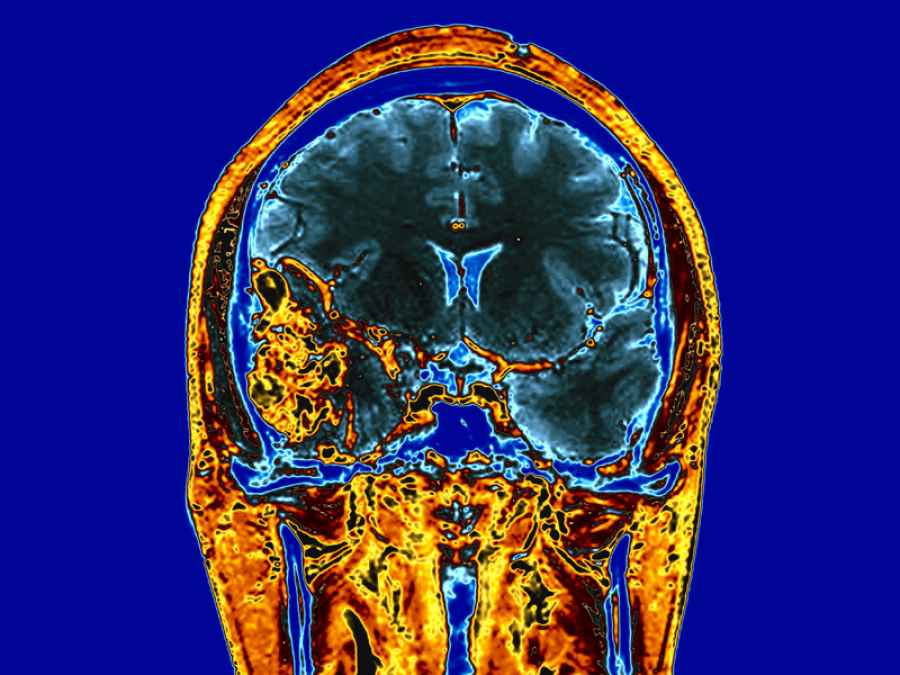

El gadolinio, que se usa como medio de contraste en las resonancias magnéticas, si se reparte dentro de las células cancerígenas podría acabar con ellas mediante la liberación de electrones tras ser golpeadas por rayos X, según una investigación publicada en la revista ‘Scientific Reports’ y cuyo objetivo es buscar la manera en que la radioterapia solo actúe sobre las células cancerosas.

Los investigadores usaron unas nanopartículas de sílice que fueron cargadas con gadolinio. Las células cancerígenas, en un cultivo 3D, efectivamente consumían las partículas después de un día de incubación, esto es, las partículas específicamente localizadas justo fuera del núcleo de la célula cancerígena.

En el centro ‘SPring-8′ de Harima, los investigadores esperaban alcanzar los rayos X monocromáticos en las muestras tumorales que estaban cargadas con nanopartículas de gadolinio.

Los rayos X alcanzaron un nivel de energía de 50,25 kiloelectron-voltios que durante 60 minutos, y destruyeron completamente las células cancerígenas de la muestra dos días después de la radiación.

Lanzando los rayos X a un nivel de energía justo debajo de la cantidad mencionada no surtía el mismo efecto. Los investigadores explican que los rayos X se lanzan de tal forma que la energía puede ser absorbida por el gadolinio. Cuando estos lo golpean, el gadolinio lanza electrones a una baja energía dentro de la célula cancerígena, dañando sus componentes vitales, incluyendo su cadena de ADN.